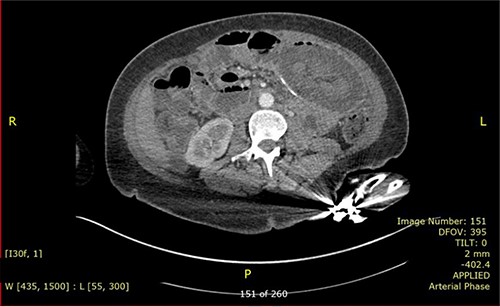

Nevertheless, the patient re-presented 4 months later with similar symptoms. She reported having no issue with bowel after the previous operation. On presentation, her blood results were unremarkable with normal inflammatory markers and lactate. Repeated CT (Fig. 3) again revealed intussusception of small bowel with signs of bowel ischaemia. She was taken to theatre for emergency laparotomy. Intraoperatively, there were dense adhesions with four quadrant purulent peritonitis and a small perforation was found on the anterior staple line of ileo-ileal anastomosis. Distal limb of small bowel had intussuscepted retrograde into the anastomosis, causing obstruction of both thickened proximal limbs. Attempt at the reduction of intussusception was unsuccessful, hence decision was made to proceed with resection and Roux-en-Y reconstruction. Ileo-ileal anastomosis was recreated with stapled side-to-side anastomosis, and roux loop was re-anastomosed just distal to it with double-layered, sutured end-to-side jejunal-ileal anastomosis. Patient made an uneventful recovery and was discharged after a week. Histology of resected small bowel segment in both operations did not show evidence of localized inflammation or neoplasia and the cause of intussusception is not apparent.

CT scan is the preferred imaging modality for early identification of intussusception [9]. Characteristic findings are target signs and multiple concentric rings as seen in this case. While CT can diagnose intussusception, there is limitation in identifying its underlying aetiology. Other imaging modalities, such as plain abdominal films or ultrasonography, can be used but is less practical in diagnostic purpose compared to CT scan.